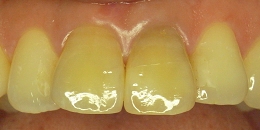

色が違い目立っている状態

上の歯の中央2本が、他の歯の色と違い、目立ってしまっている状態です。

セラミックに換えた状態

セラミックの歯に換えました。

周りの歯の色と整い、自然な状態になりました。